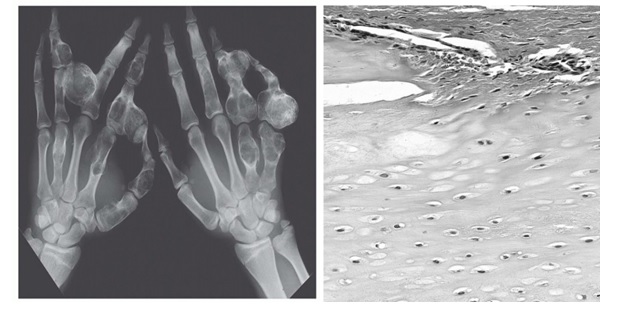

Wieloogniskowe zmiany typu chrzęstniak umiejscowione niesymetrycznie, zwykle z zajęciem kości śródręcza lub kości stóp (przedstawione na rycinach) są określone jako: